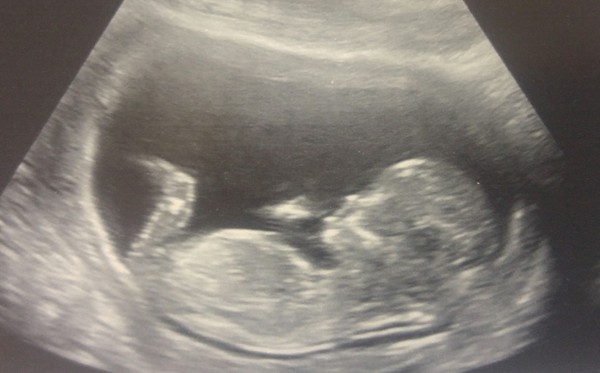

Ginger I've tried the nub theory and have convinced myself it's a girl

but probably totally wrong or it will be a fluke!